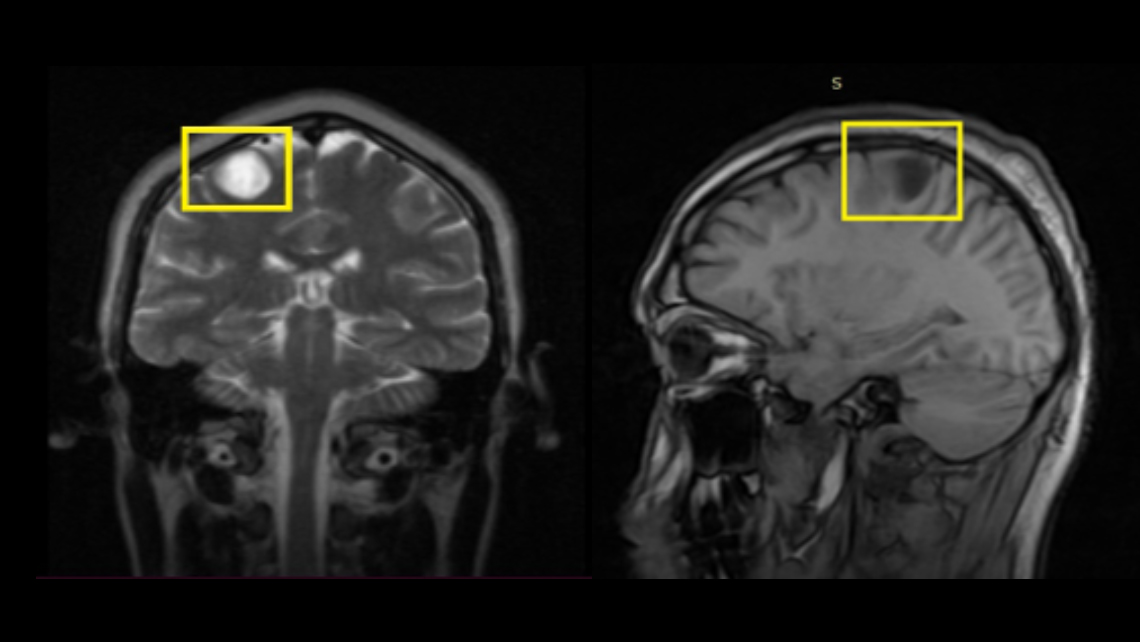

Paciente masculino de 25 años de edad que refiere episodios convulsivos desde hace cuatro días, es evaluado por el servicio de neurología y se solicita estudio de resonancia magnética, evidenciándose lo siguiente:

Lesión intraaxial de comportamiento quístico en todas las secuencias, ovalada, de bordes definidos, con capsula que realza tras la administración de gadolinio, mide 19 x 14.8 x 15.1 mm y pequeño foco central de mayor densidad, no genera efecto de masa, ni presenta edema perilesional, a considerar naturaleza infecciosa (neurocisticercosis).